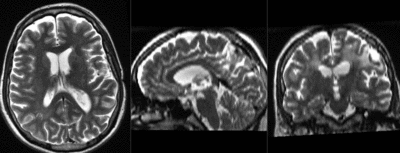

this is the fixed T2 reference image. All images are aligned into this space lleft this is the DTI Baseline scan, to be registered with the T2 this is the DTI tensor image, in the same orientation as the DTI Baseline

fixed image/target

T2

moving image 2a

DTI baseline

moving image 2b

DTI tensor